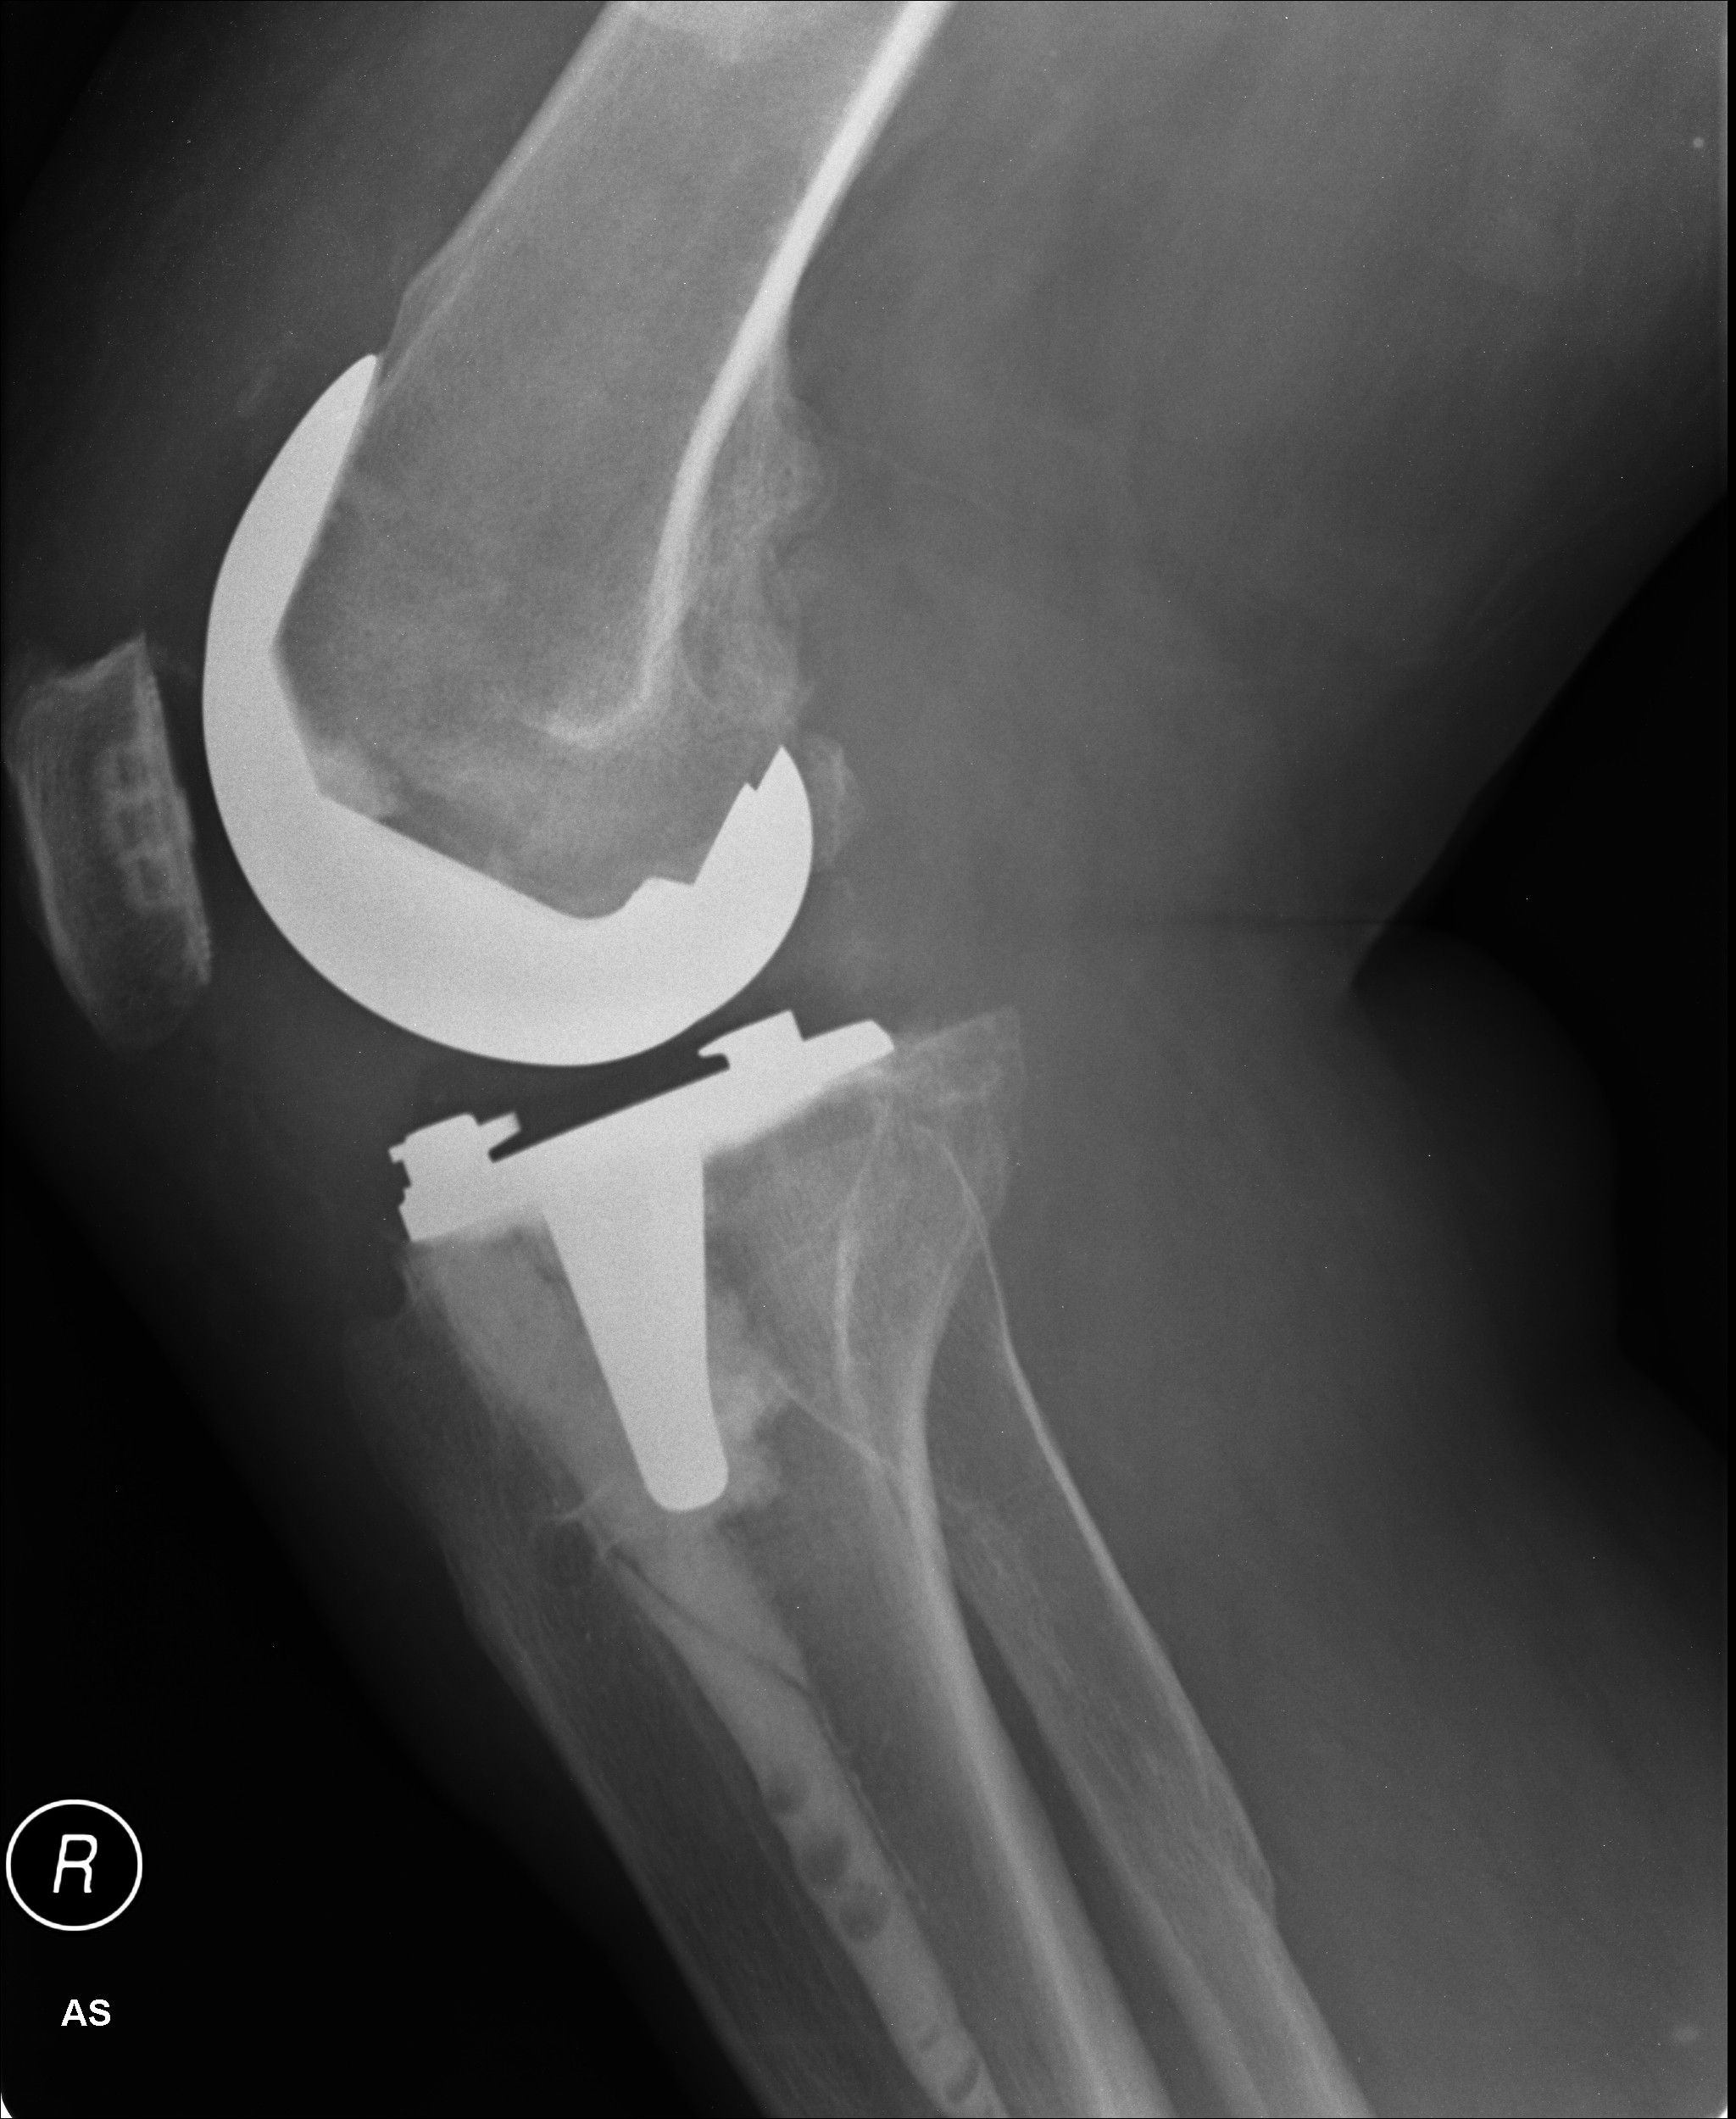

Medicinski vsadki oziroma implantati, ki prihajajo neposredno v stik z živim tkivom, predstavljajo pomemben napredek v razvoju medicine. Omogočajo nadomestitev obrabljenega ali poškodovanega dela kosti ali sklepa, lahko pa le nudijo podporo na obrabljenem in poškodovanem delu. Med najbolj znanimi primeri implantatov lahko naštejemo kolčni sklep, umetno srčno zaklopko in dele zobovja. Vstavljanje implantatov je invaziven kirurški poseg v telo, ki se lahko močno zaplete. Med najpogostejše zaplete sodijo bolečina, otekanje in mikrobne okužbe implantatov, ki se lahko pojavijo med operacijskim posegom ali po njem. Zaradi burnega odziva telesa na tujek lahko pride tudi do zavrnitve implantata.